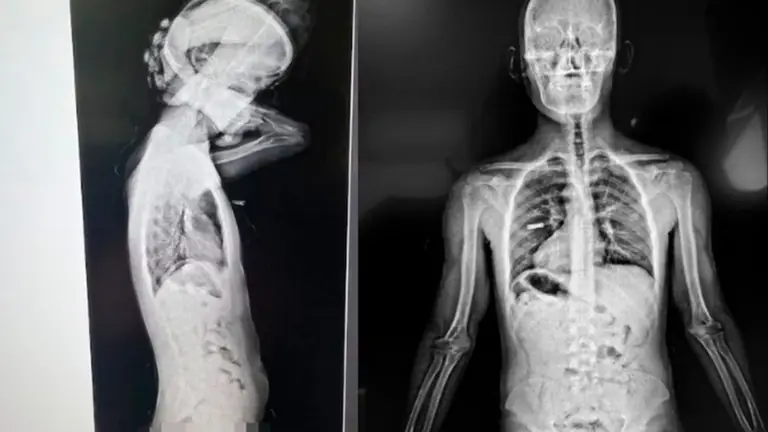

Tras ser interrogados, ambos fueron trasladados a las oficinas de la Aduana ubicadas en el Puente Internacional Horacio Guzmán, donde se les practicó un escáner corporal. El estudio no intrusivo permitió detectar la presencia de cuerpos extraños en la zona abdominal, aunque los implicados negaron haber ingerido cápsulas.

Ante esta situación, se dio intervención a la Unidad Fiscal Federal de Jujuy, que ordenó el traslado de los sospechosos al Hospital Dr. Jorge Uro de La Quiaca. Allí, mediante estudios de rayos X, se confirmó la presencia de elementos extraños en sus organismos, por lo que quedaron internados bajo custodia.